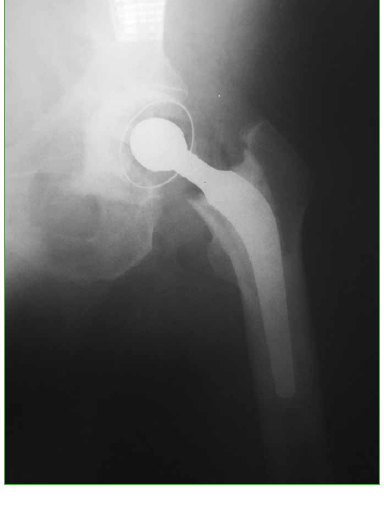

Hip fractures in patients with ipsilateral limb amputations are uncommon injuries that pose a challenge for orthopedic surgeons. In this article, we present our experience in the treatment of a 63-year man with left transfemoral amputation, who suffered a left femoral neck fracture after a fall from standing height. Proper placement of the prosthesis is essential to achieve good postoperative clinical outcomes. A Steinmann pin was inserted into the greater trochanter to facilitate exposure and component placement. No clinical or radiological complications were detected in a 15-month follow-up. We believe that the correct placement of a Steinmann pin is a good alternative that provides adequate control over the extremity when performing an arthroplasty, thus reducing the risks for prosthesis displacement and shortening the surgical time.